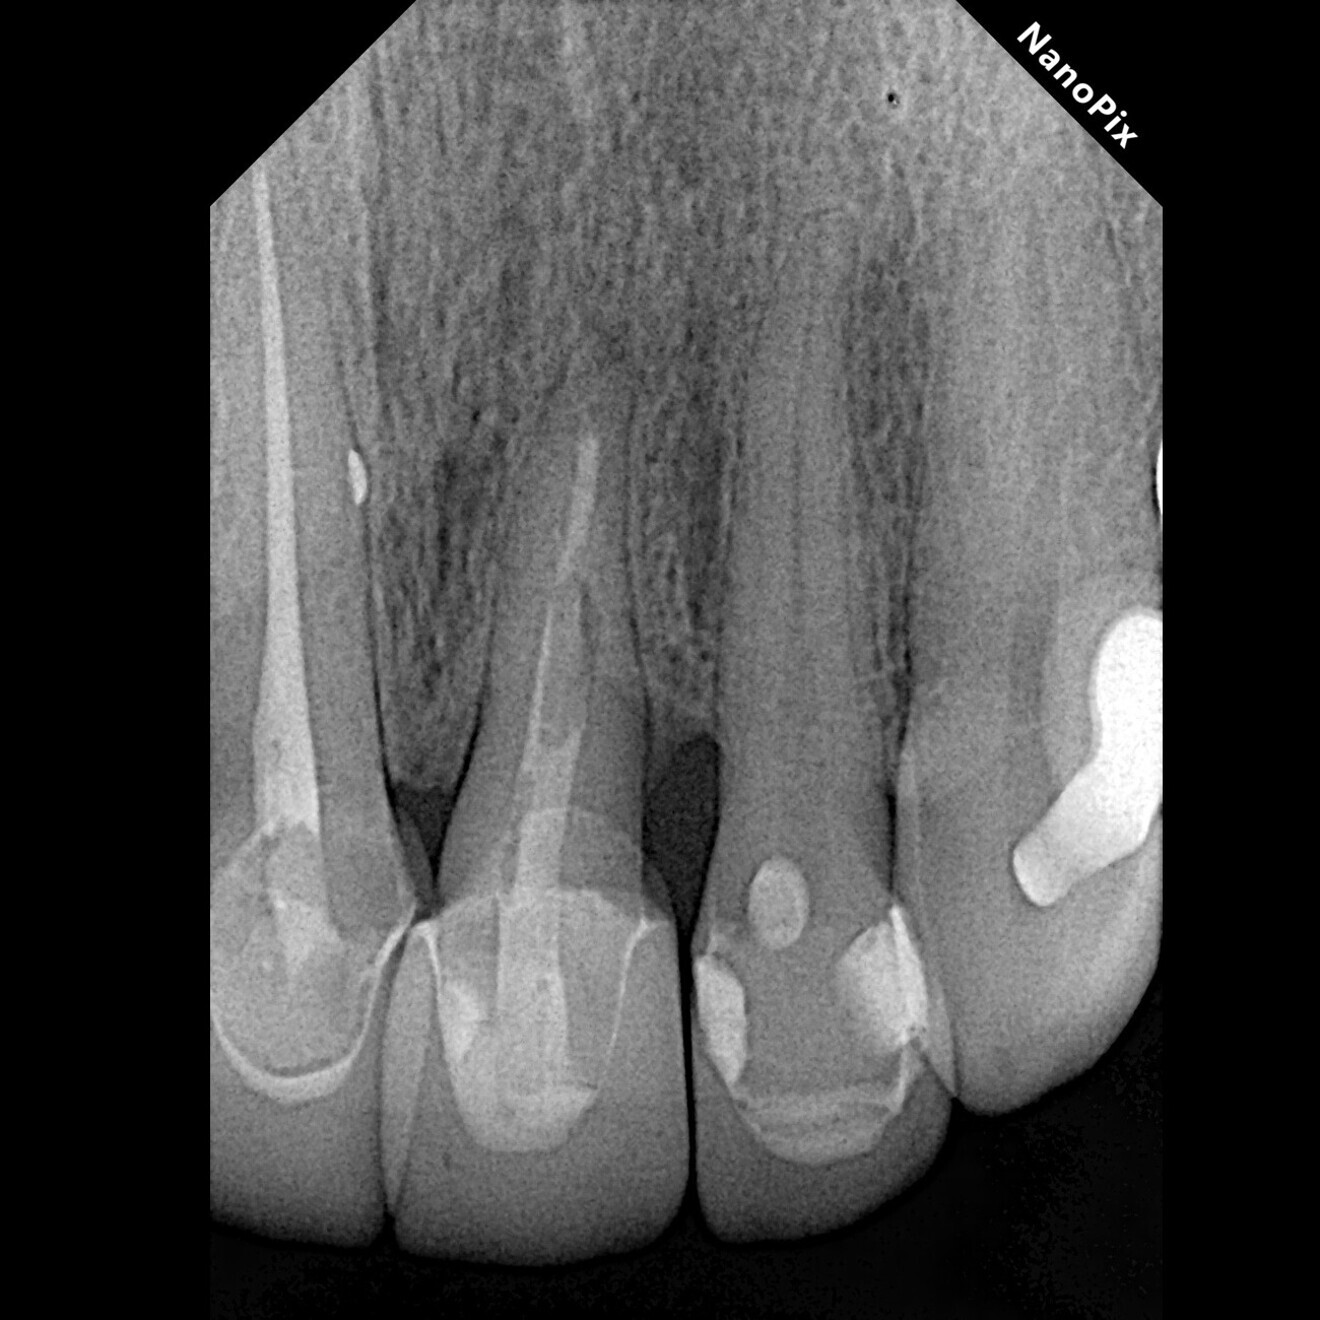

Fig. 2: Post-op radiograph of the tooth extruded by approximately 6 mm and rotated by 180°, locating the deeper zone of the fracture towards the mesial aspect.

After removing the metal–porcelain crown and disinfecting the affected area using a gauze dampened with 2% chlorhexidine (GLUCO-CHeX 2%, CERKAMED), syndesmotomy was performed with a No. 15c scalpel, followed by luxation of the root using a small periotome. Luxation forces were applied only to the first 3 mm of the radicular structure at the mesial aspect with the objective of avoiding damage to the periodontal ligament, which was intended to remain in an infra-osseous position. Once the tooth had been loosened, it was extruded by approximately 6 mm and rotated by 180° (Fig. 2). The rotation was performed with the purpose of positioning healthy periodontal ligament fibres in the distal area because the crestal bone already had an oblique defect at this site. Usually the bone follows the extruded periodontal ligament fibres during this type of procedure, making vertical bone gain possible.8, 15, 16 The rotation also allowed us to limit the extent of extrusion. The extrusion and rotation were managed with forceps, grasping only the coronal portion of the tooth, which was planned to remain in a supra-osseous position after the treatment.